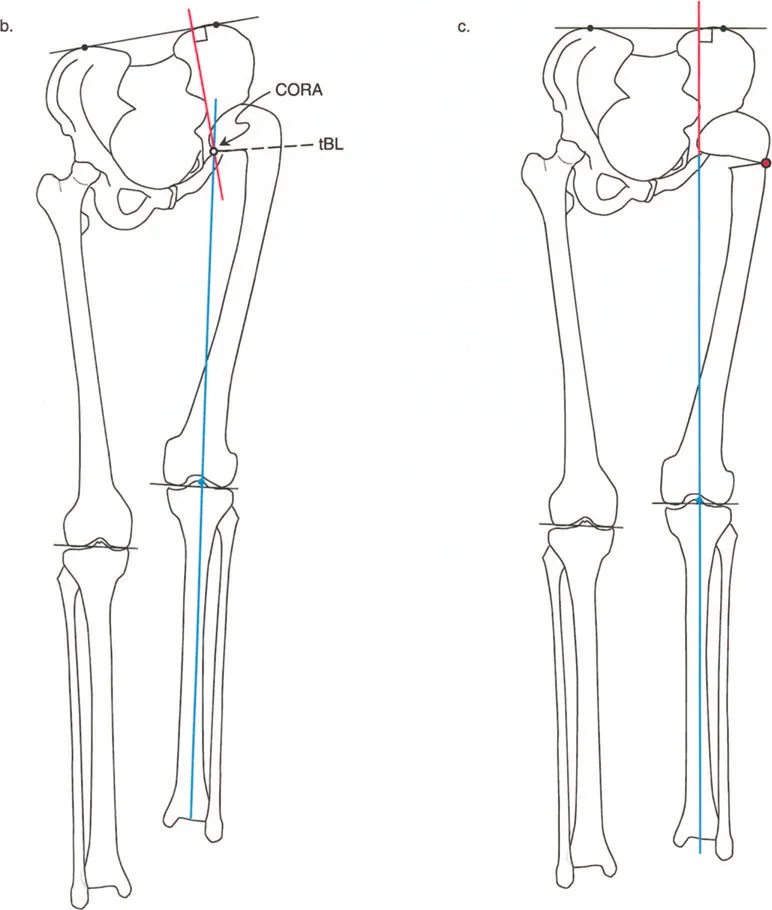

يُعد فهم العلاقة بين مركز دوران الانحراف (CORA) ومستوى قطع العظم أمرًا بالغ الأهمية.

- قاعدة قطع العظم 1: إذا تم إجراء قطع العظم بالضبط عند مستوى CORA، فإن تصحيحًا زاويًا فقط (بفتح أو إغلاق وتد) يكون مطلوبًا. يتم استعادة المحور الميكانيكي، ولن يحدث أي إزاحة لقطعي العظم.

- قاعدة قطع العظم 2: إذا كان CORA يقع قريبًا (أو بعيدًا) عن المستوى الفعلي لقطع العظم، فيجب إزاحة الجزء البعيد لاستعادة المحور الميكانيكي. سيؤدي التقويم الزاوي البحت عند مستوى بعيد عن CORA إلى تشوه إزاحة ثانوي.

في الجزء القريب من عظم الفخذ، غالبًا ما يقع CORA لتشوه سهمي في الجزء العلوي من عنق الفخذ أو حتى داخل رأس الفخذ. ومع ذلك، لأسباب تتعلق بالشفاء البيولوجي وتثبيت الأجهزة، غالبًا ما يتم إجراء قطع العظم في مستوى أدنى بكثير، عادة في منطقة ما بين المدورين أو تحت المدور.

نظرًا لأن CORA يقع قريبًا من خط قطع العظم، فإن الإزاحة إلزامية تمامًا أثناء التصحيح:

* لتشوهات الانبساط (التي تتطلب قطع عظم للانثناء): يجب إزاحة عمود الفخذ للأمام.

* لتشوهات الانثناء (التي تتطلب قطع عظم للانبساط): يجب إزاحة عمود الفخذ للخلف.

سيؤدي الفشل في إزاحة عمود الفخذ بشكل مناسب إلى تشوه إزاحة ثانوي، مما يُغير المحور الميكانيكي للطرف السفلي (انحراف المحور الميكانيكي - MAD) وقد يسبب ميلان خط المفصل عند الركبة.